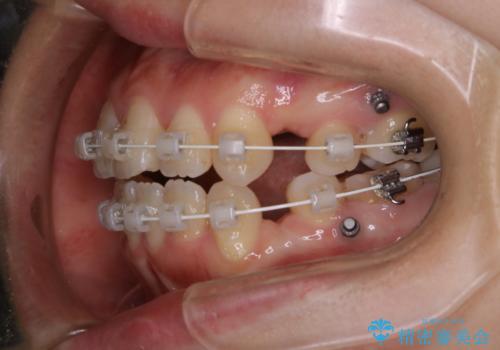

- ワイヤー矯正中のメンテナンスでPMTCを希望されました。染め出しを行い、歯ブラシ指導とPMTC30分コースを行いました。

毎日しっかりと磨いているようでも、装置の周りや歯と歯の間・歯と歯茎の間に磨き残しが残ってしまいます。そのため磨き残しをチェックする『染め出し剤』を使用すると明確に磨き残しを見ることができます。

染め出されている部分の磨き残しは、毎日の習慣として歯ブラシをしていてもいつも磨けてない部分です。